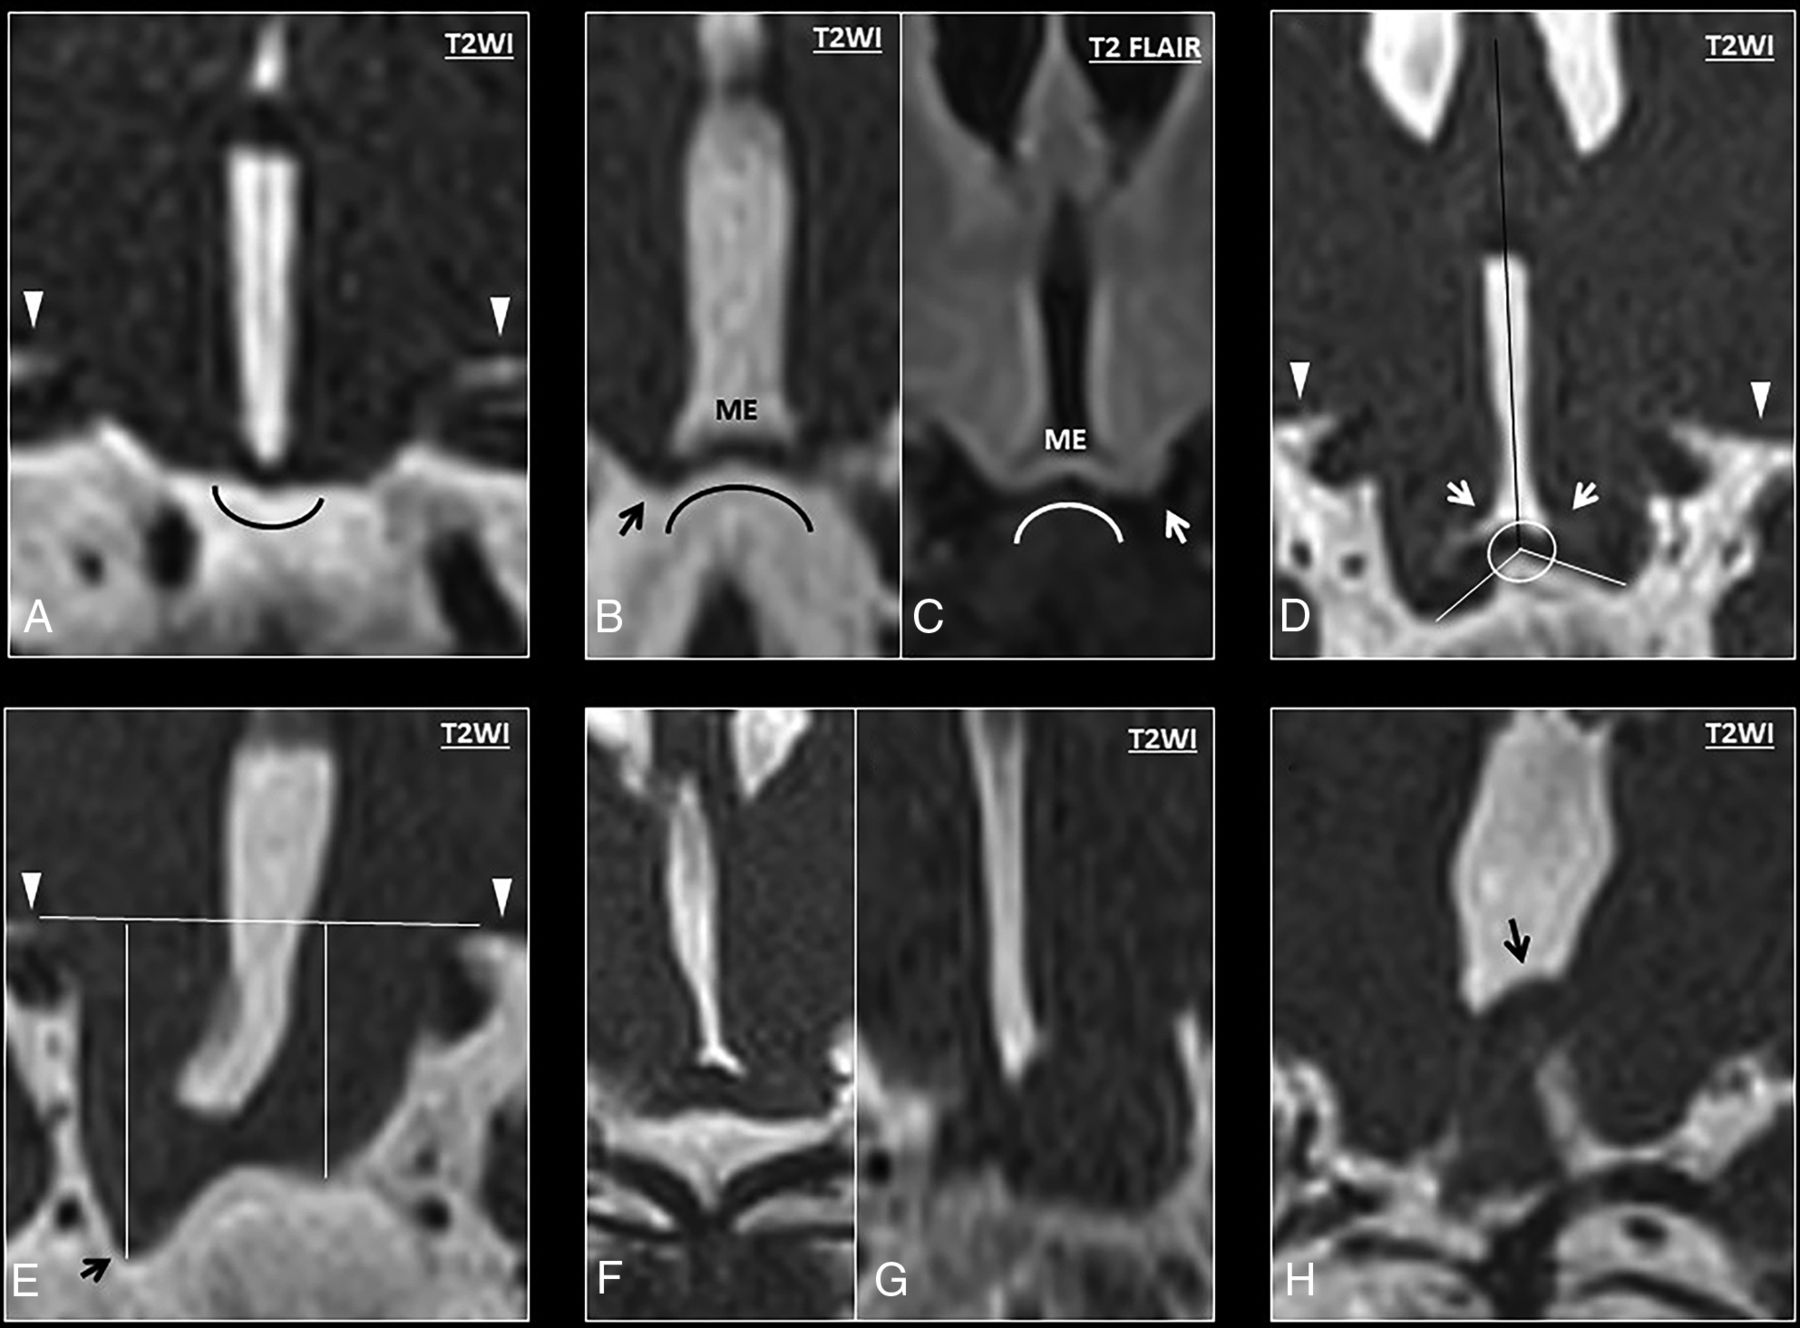

Six patients with DFNX2 showed concave morphology of the medial eminence in relation to the pituitary gland, with the lowest point of the ventromedial hypothalamus below the medial eminence (κ = 0.78). Two patients with DFNX2 showed convex morphology, and 2 had suboptimal images of the hypothalamus on the coronal plane (Fig 3A–C). None of the controls showed concave medial eminence morphology (P < .001). To further characterize the abnormal hypothalamic concavity on the coronal plane, we measured the coronal hypothalamic–septum pellucidum angle. The first component of this angle was a straight craniocaudal line along the septum pellucidum that crossed the vertex of the concave or convex medial eminence (Fig 3D, black line). The second component was another straight line originating from the previously mentioned vertex of the medial eminence to the most caudal end of the ventromedial hypothalamus; the angle between these 2 lines on either side was named the right and left coronal hypothalamic–septum angle, respectively. The right coronal hypothalamic–septum angle of patients with DFNX2 measured 115.5° ± 17.34°, while it measured 79° ± 8.05° in age-matched controls (P < .001). The left coronal hypothalamic–septum angle of patients with DFNX2 measured 113.87° ± 16.87°, while it measured 81.87° ± 9.32° in age-matched controls (P < .001). The individual intraclass correlation coefficient was 0.88 and 0.77 on the right and left sides, respectively.

A, Coronal T2 anatomy of a normal hypothalamus showing the classic convex morphology of the medial eminence. B–H, High-resolution coronal T2 images show progressive bending of the ventromedial hypothalamus (from mild to severe). B, High-resolution coronal T2 image shows abnormal concavity at the junction between the ventromedial hypothalamus and the medial eminence, with a low-lying ventromedial hypothalamus (black arrow) in relation to the medial eminence (ME). These findings show an abnormal concave morphology of the hypothalamus in relation to the pituitary gland. C, Coronal T2 FLAIR image of another patient with DFNX2, which demonstrates isointense signal compared with the adjacent globus pallidus. Note again the characteristic bending of the ventromedial hypothalamus and its caudal location in relation to the medial eminence (white arrow). D, Measurement of the angle between the tip of the ventromedial hypothalamus and the septum pellucidum (white arrows). E, Measurement of the craniocaudal length of the ventromedial hypothalamus at the lowest point (black arrow) in relation to the basal forebrain (horizontal line). The basal forebrain (white arrowheads) is also indicated on images A and D. F and G, In some cases, the low-lying hypothalamus and the folding are so severe that some hypothalamic segments appear masslike, though the overall appearance is in keeping with diffuse folding. H, Severe hypothalamic bending in a patient with DFNX2, which shows cranial folding of the hypothalamus (black arrow) apart from the typical low-lying or hanging infundibular nucleus (not shown in this image).

Another measurement was proposed to further characterize the hypothalamic concavity and low-lying ventromedial hypothalamus: the craniocaudal length between the basal forebrain and the lowest point of the ventromedial hypothalamus. The first component of this measurement was a straight line over the inferior edge of the basal forebrain (Fig 3E, white arrowheads), and the second component was a perpendicular line linking this line with the lowest point of the ventromedial hypothalamus on either side (Fig 3E, black arrow). The right forebrain-hypothalamus length in DFNX2 was 7.15 ± 3.02 mm, while it was 4.26 ± 0.7 mm in age-matched controls (P < .001). The left forebrain-hypothalamus length in DFNX2 measured 6.9 ± 2.1 mm, while it was 4.21 ± 0.73 mm in controls (P < .001). The individual intraclass correlation coefficient was 0.92 and 0.87 on the right and left sides, respectively.